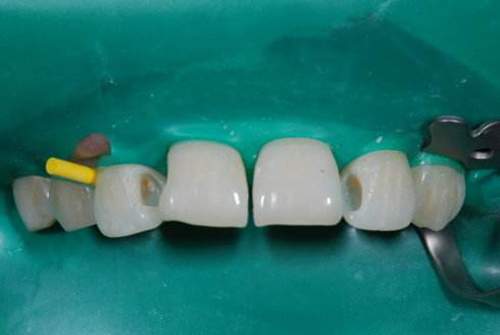

橡皮障术区隔离法:是一种真正意义上的“无菌”操作技术,橡皮障也已经发展成为一种保护医生和患者的精密装置。可防止患者吸入或吞入器械、牙碎片、冲洗液或药物;提供一个没有唾液、血液和其他组织液污染的、清洁的操作空间;保护口腔软组织不受到意外伤害;保持术者视野清晰,提高工作效率;防止医源性交叉感染。

1、隔离及感染控制。将患者被治疗的牙齿与口腔环境分开,避免了口腔中的细菌向被治疗牙齿的传播,保证被治疗牙齿处于相对无菌的环境里,有助于减少感染、提高治愈率,还避免口腔中唾液对被治疗牙的污染,提高粘接的成功率。